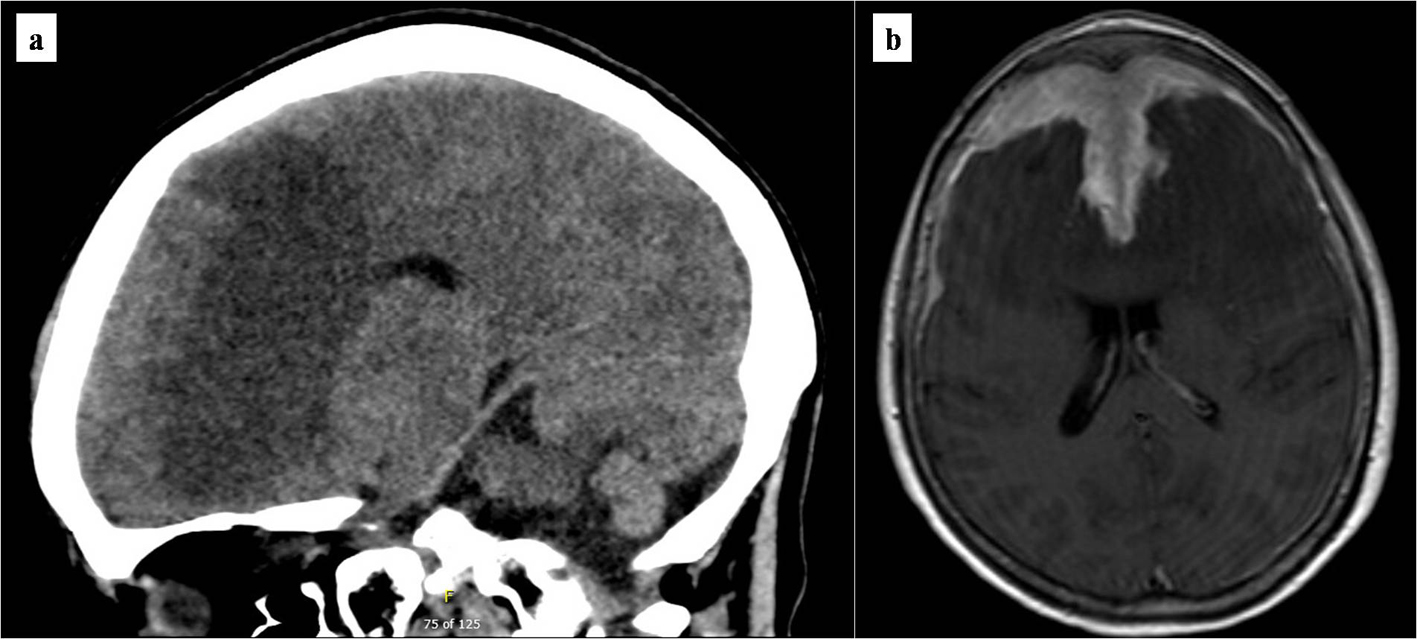

Non-contrasted computed tomography (CT) scan showed a prominent bifrontal white matter hypodensity involving the periventricular regions along with a poorly marginated region of hyperdensity along the anterior cranial vault (Fig. 1a). Magnetic resonance imaging (MRI) showed a plaque-like extra-axial, T1/T2 isointense mass over the bifrontal convexity which exerted a mass effect. There was no evidence on gradient sequences to suggest hemorrhage or diffusion restriction to suggest infection (Fig. 1b). The initial differential diagnosis included meningioma, dural metastases, hypertrophic pachymeningitis, and lymphoma. The patient underwent frontal craniotomy for biopsy of the abnormally thickened dura. Histopathology of the mass revealed a dense infiltrate of small lymphocytes, composed predominantly of CD20 positive B cells aberrantly expressing CD43 by immunohistochemistry (Fig. 2). Flow cytometry demonstrated that the B cells were lambda-restricted and were negative for CD5, CD10, and CD200. The immunophenotype was most consistent with MZL [11]. CT of the chest, abdomen, and pelvis showed no other abnormalities. Lumbar puncture was initially deferred due to concerns regarding intracranial mass effect. She was treated with dexamethasone 4 mg twice daily and discharged after cognitive improvement.

![]() Click for large image | Figure 1. Brain imaging at presentation. (a) Initial non-contrasted computed tomography scan of the brain. Marked bifrontal white matter hypodensity extends across the corpus callosum with mass effect on the frontal horns of the lateral ventricles. In addition, there is a large poorly marginated region of hyperdensity along the anterior falx and anterior cranial vault which appears extra-axial. (b) T1/2-weighted brain MRI. Bifrontal extra-axial mass with extensive dural tail with invasion into both frontal lobes and extensive edema extending across the corpus callosum. MRI: magnetic resonance imaging. |